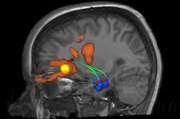

Animation der Lage des Hippocampus im Gehirn, mit farblich gekennzeichneten Unterstrukturen